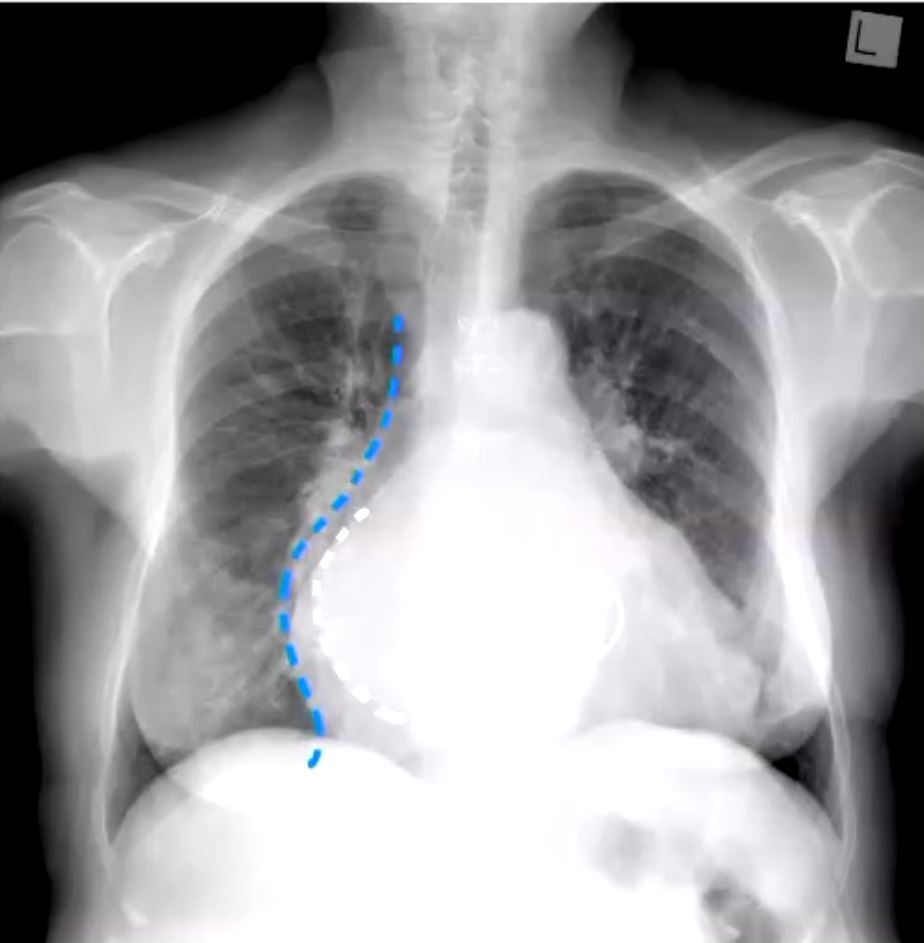

how can you see LA enlargement on chest xray

doubledensity

la enlargement double density

mitral stenosis ra enlargemenet elevated l bronchus